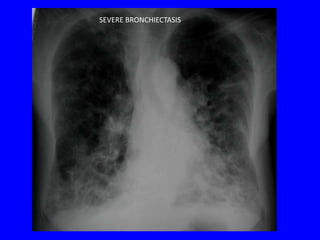

SEVERE BRONCHIECTASIS

Circle filled

with air

RINGS (CYSTS) CONTAINING AIR-FLUID LEVELS